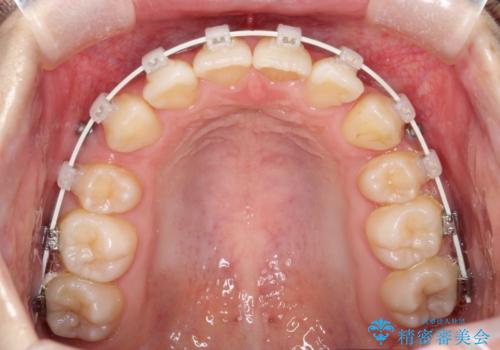

ワイヤーによる抜歯矯正でガタガタの改善

- 前歯のがたがたを主訴に来院されました。

上下の前歯が前方に傾斜しているのもあり、内側に前歯をひっこめるために上下左右の歯を1本ずつ抜歯して矯正することとしました。

ガタガタも改善しましたが、前歯が内側に引っ込むことにより口元もすっきりして、唇が閉じやすくなりました。